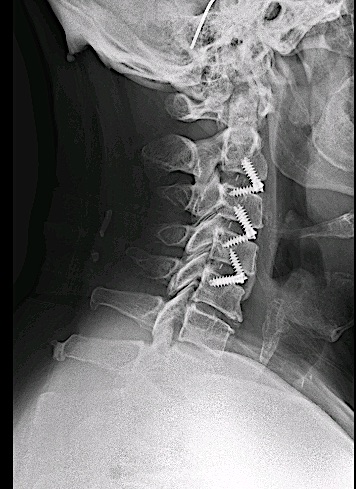

Control de 6 meses

El control postoperatorio RM cervical 6 meses demuestra adecuada descompresión de canal y adecuada aceptación de material de osteosíntesis.